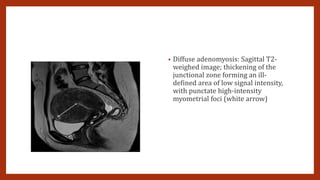

• Diffuse adenomyosis: Sagittal T2-

weighed image; thickening of the

junctional zone forming an ill-

defined area of low signal intensity,

with punctate high-intensity

myometrial foci (white arrow)

MRI • MR imagingmay be equal or slightly superior to TVS (Dueholm, 2001; Reinhold, 1996). Thus, MR imaging may be most appropriate when the diagnosis is inconclusive, when further delineation would affect patient management, or when coexisting uterine myomas distort anatomy (American College of Obstetricians and Gynecologists, 2014b). • T2-weighted sequences are key for diagnosing adenomyosis • Adenomyosis appears as increased thickness of the junctional zone, forming an ill-defined area of low signal intensity on T2, representing the smooth muscle hyperplasia accompanying the heterotopic endometrial tissue. This aspect is frequently associated with bright foci on T2-weighted images, which represent foci of heterotopic endometrial tissue, cystic dilatation of endometrial glands or haemorrhagic foci. • Adenomyosis is mainly located in the fundus [20] and commonly observed in the posterior wall. The typical appearance is a large, rand asymmetric uterus, with a maximum junctional zone thickness of at least 12 mm and punctate high-intensity myometrial foci [17]. • There are two forms of adenomyosis: diffuse, in which foci of adenomyosis are distributed throughout the uterus (Fig. 1), and focal form, also named adenomyoma, when it affects a limited area (Fig. 2). The most frequent finding for the diagnosis of adenomyosis is thickening of the junctional zone, with a thickness exceeding 12 mm being highly predictive of the diagnosis

• Diffuse adenomyosis:Sagittal T2- weighed image; thickening of the junctional zone forming an ill- defined area of low signal intensity, with punctate high-intensity myometrial foci (white arrow)